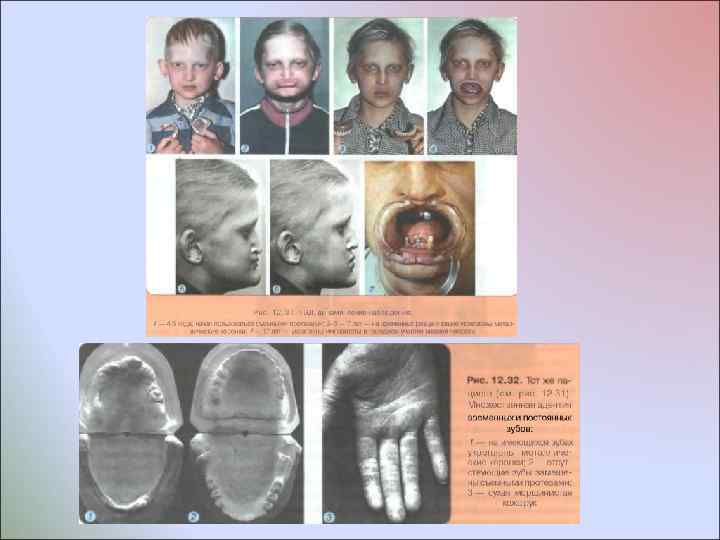

Врожденное отсутствие более 10 постоянных зубов У некоторых пациентов отмечают врожденное множественное отсутствие зубов без изменения развития других производных эктодермы У пациентов с ГЭД мало волос, они светлого цвета, брови недоразвиты, ресницы растут кустиками; кожа сухая, морщинистая, нередко пигментированная вокруг глаз и рта; ногти деформированы; зрение нарушено - пользуются очками с детства. По эстетическим отклонениям, состоянию психоневротического статуса и общим нарушениям организма пациенты этих двух групп различаются. Общим для них является лишь врожденное отсутствие зачатков более 10 постоянных зубов

Врожденное отсутствие более 10 постоянных зубов У некоторых пациентов отмечают врожденное множественное отсутствие зубов без изменения развития других производных эктодермы У пациентов с ГЭД мало волос, они светлого цвета, брови недоразвиты, ресницы растут кустиками; кожа сухая, морщинистая, нередко пигментированная вокруг глаз и рта; ногти деформированы; зрение нарушено - пользуются очками с детства. По эстетическим отклонениям, состоянию психоневротического статуса и общим нарушениям организма пациенты этих двух групп различаются. Общим для них является лишь врожденное отсутствие зачатков более 10 постоянных зубов

Перед началом ортодонтического лечения и зубопротезированием проводят обследование пациента, включающее: • Изучение фотографий лица с детского возраста для выявления смешений нижней челюсти, асимметрий лила, укорочения его нижней части • Сбор анамнеза, уточнение возрастного периода потери временных и постоянных зубов • Рентгенологический контроль (ОПТГ челюстей) -определение величины и локализации дефектов зубных рядов: наклонов, корпусного смешения соседних и противостоящих зубов, нарушений окклюзии зубных рядов, наличия и степени формирования всех постоянных зубов, рассасывания корней всех временных зубов • Изучение моделей челюстей, особенностей дефектов зубных рядов, формы и уровня расположения гребня альвеолярного отростка • Клиническое определение морфофункционального состояния зубочелюстной системы, в том числе ВНЧС

Перед началом ортодонтического лечения и зубопротезированием проводят обследование пациента, включающее: • Изучение фотографий лица с детского возраста для выявления смешений нижней челюсти, асимметрий лила, укорочения его нижней части • Сбор анамнеза, уточнение возрастного периода потери временных и постоянных зубов • Рентгенологический контроль (ОПТГ челюстей) -определение величины и локализации дефектов зубных рядов: наклонов, корпусного смешения соседних и противостоящих зубов, нарушений окклюзии зубных рядов, наличия и степени формирования всех постоянных зубов, рассасывания корней всех временных зубов • Изучение моделей челюстей, особенностей дефектов зубных рядов, формы и уровня расположения гребня альвеолярного отростка • Клиническое определение морфофункционального состояния зубочелюстной системы, в том числе ВНЧС

Основные задачи комплексного стоматологического лечения пациентов с множественной адентией • Улучшение эстетики лица и улыбки • Улучшение функций глотания и жевания, что позволяет расширить диету ребенка и способствует нормализации его физиологического и соматического развития • Создание условий для рационального зубочелюстного протезирования • Нормализация положения языка в покое и во время функций • Улучшение речи, включая произношение шипящих и свистящих звуков • Улучшение психологического и эмоционального состояния пациента

Основные задачи комплексного стоматологического лечения пациентов с множественной адентией • Улучшение эстетики лица и улыбки • Улучшение функций глотания и жевания, что позволяет расширить диету ребенка и способствует нормализации его физиологического и соматического развития • Создание условий для рационального зубочелюстного протезирования • Нормализация положения языка в покое и во время функций • Улучшение речи, включая произношение шипящих и свистящих звуков • Улучшение психологического и эмоционального состояния пациента